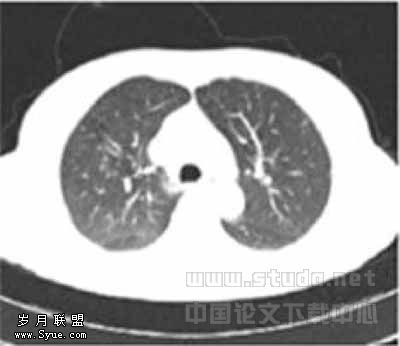

49例图像中,LD1与LD2扫描各有2例图像质量为良好(图1,2),其余均为优秀(图3,4),1例LD扫描图像比SD扫描图像清晰,原因是LD扫描时患者吸气充分而SD扫描时患者吸气不足。

图1,2分别为同一层面的常规剂量与低剂量CT,可见少量伪影,不影响观察肺结节图3,4分别为同一层面的常规剂量与低剂量CT图像,示未见伪影图3示小于5mm肯定肺结节(→?)和模糊肺结节(←?),图4分别显示为肯定(→?)、未见(←?)